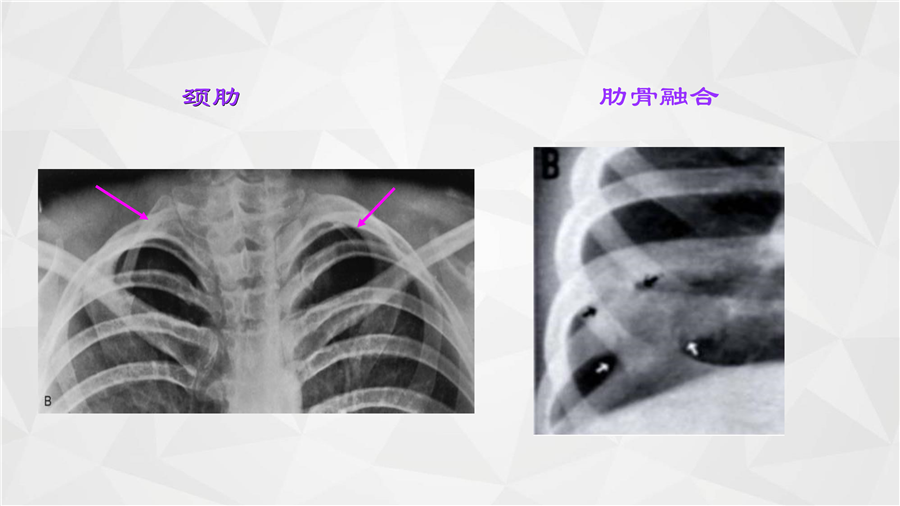

呼吸系统一